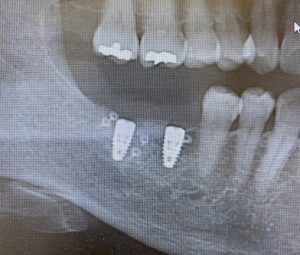

当院での骨造成の症例です

骨造成から三ヶ月 インプラント埋入時のレントゲン写真